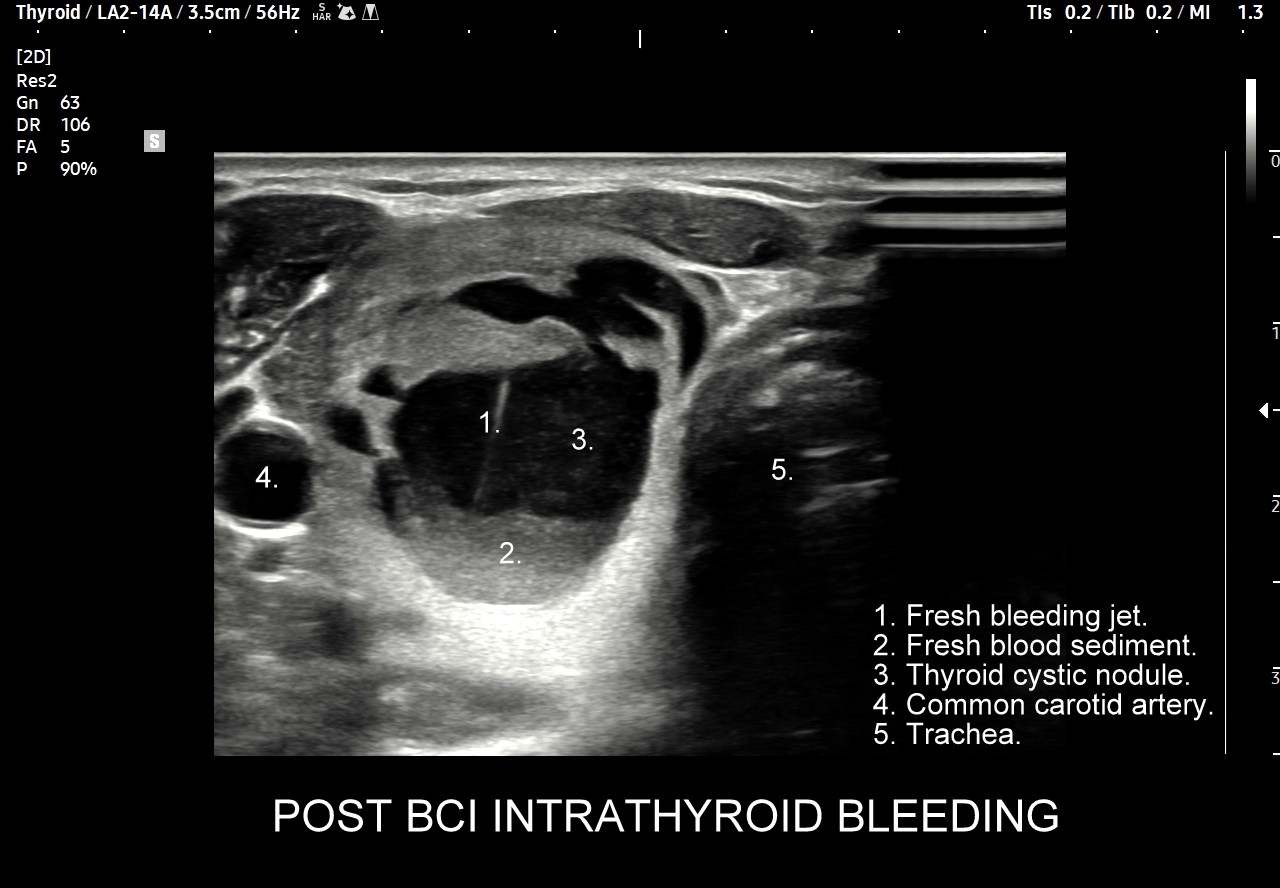

Multiparametryczne badanie USG (MPUS) jest rozwinięciem klasycznego USG tarczycy i szyi pod postacią jednoczasowego zastosowania różnorodnych technologicznie trybów obrazowania USG, zarówno tzw. „nowych”, jak i „starych”. Wśród nowych najważniejszym jest obrazowanie mikrounaczynienia (MVI / MVF), w dalszej kolejności tryb elastograficzny oraz B-flow. Wymienione „nowe” modalności w połączeniu ze „starymi”, przede wszystkim z Dopplerem spektralnym i color-Dopplerem, stanowią rdzeń nowoczesnej ultrasonografii MPUS, gdyż umożliwiają pozyskanie znacznie większej ilości informacji z badania USG szyi w porównywalnym przedziale czasowym, a przez to uzyskanie jego większej wartości diagnostycznej.

Przykładowo badanie MPUS umożliwia różnicowanie guzów, ocenę żywotności tkanek i biologii nowotworów, poprawia obrazowanie dużych naczyń krwionośnych oraz ocenę podejrzanych torbieli. Z kolei zastosowanie badania USG z kontrastem (CEUS), jako kolejnej modalności rozszerzającej MPUS, daje w wyselekcjonowanych przypadkach korzyści m. in. w postaci różnicowania i oceny zmian ogniskowych, czy oceny skuteczności terapii ablacyjnych.